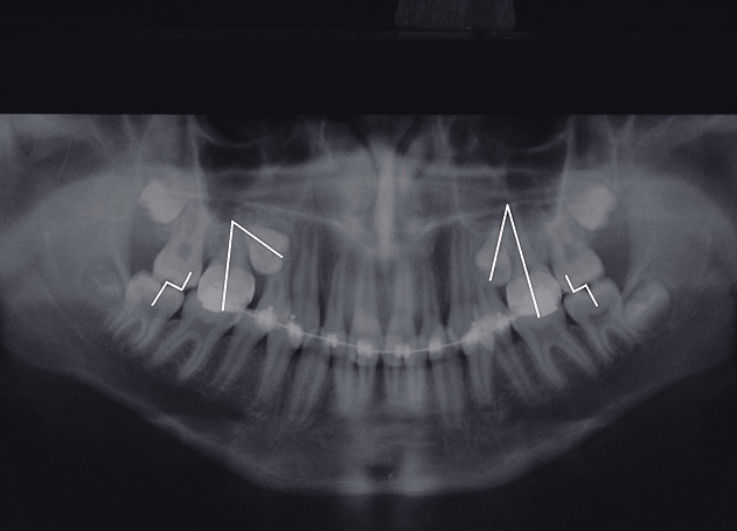

Дентальная галерея: ретинированный зуб клык и его лечение

Раздел: Компас решений